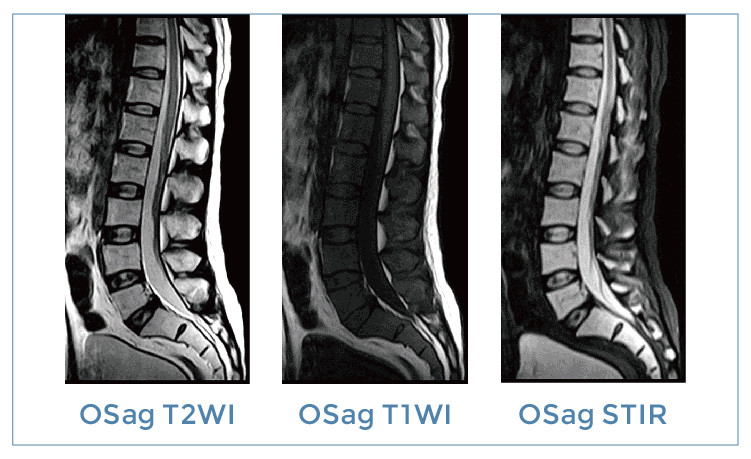

【朗润影像档案】20190830磁共振影像病例结果讨论

【朗润影像档案】磁共振影像病例分享(编号20190830)